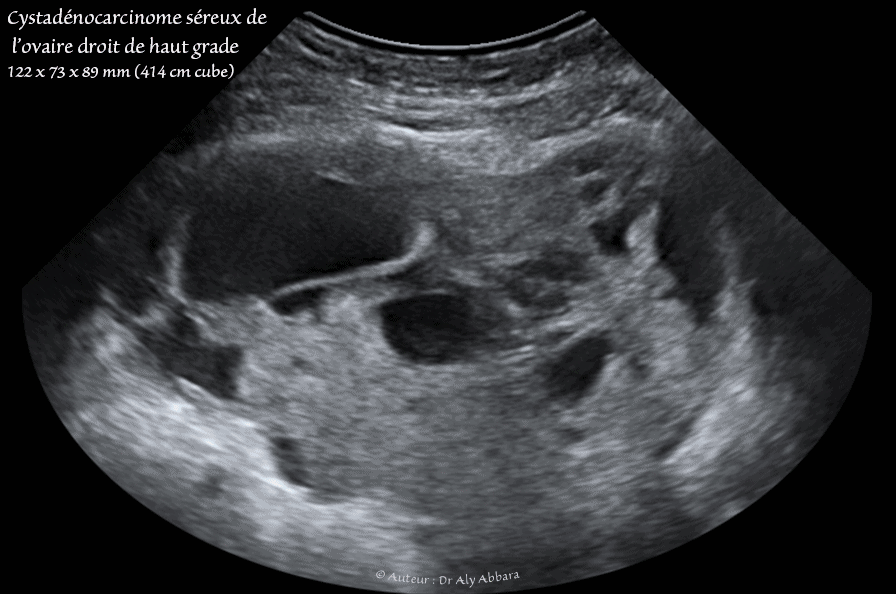

Images échographiques et cliniques animées montrant, chez une femme âgée de de 47 ans, une tumeur ovarienne droite, de type mixte, solide et kystique multiloculaire, de 122 x 73 x 89 mm de diamètre (414 cm3).

L'acte opératoire réalisé en urgence pour un tableau clinique fait évoquer, en plus de la présence de cette formation tumorale, le diagnostic d'une torsion de l'ovaire droit.

En per-opératoire, une torsion de cette tumeur ovarienne droite a été constatée ; pas d'ascite ; pas de végétations exophytiques ovariennes, mais elle a été observée la présence des implants tumoraux (exophytiques) sur la trompe droite et son pavillon. L'utérus et les annexes gauches sont sains et le reste de l'exploration de la cavité abdominale et sans particularité.

L'examen anatomopathologique conclut qu'il s'agit d'un cystadéno-carcinome séreux de l'ovaire droit, de haut grade, envahissant la trompe droite au niveau de son pavillon et sa paroi : il s'agit d'un envahissement partiel, de dehors en dedans. L'aspect histologique des ces implants est similaire à celui de la tumeur de l'ovaire (cellules tumorales très volumineuses, avec atypies cytonucléaires très marquées et des mitoses très nombreuses).